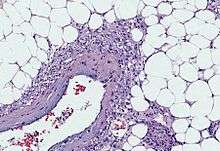

Angiomyolipomas are tumours consisting of perivascular epithelioid cells (cells which are found surrounding blood vessels and which resemble epithelial cells). A tumour of this kind is known as a PEComa, from the initials of perivascular epithelioid cell. Older literature may classify them as hamartomas (benign tumours consisting of cells in their correct location but forming a disorganised mass) or choristoma (benign tumours consisting of normal cells in the wrong location). PEComas are themselves a kind of mesenchymal tumour which involves cells that form the connective tissue, cardiovascular and lymphatic systems.[2]

An angiomyolipoma is composed of varying proportions of vascular cells, immature smooth muscle cells and fat cells.[2] These three components respectively give rise to the components of the name: angio-, myo- and lip-. The -oma suffix indicates a tumour.